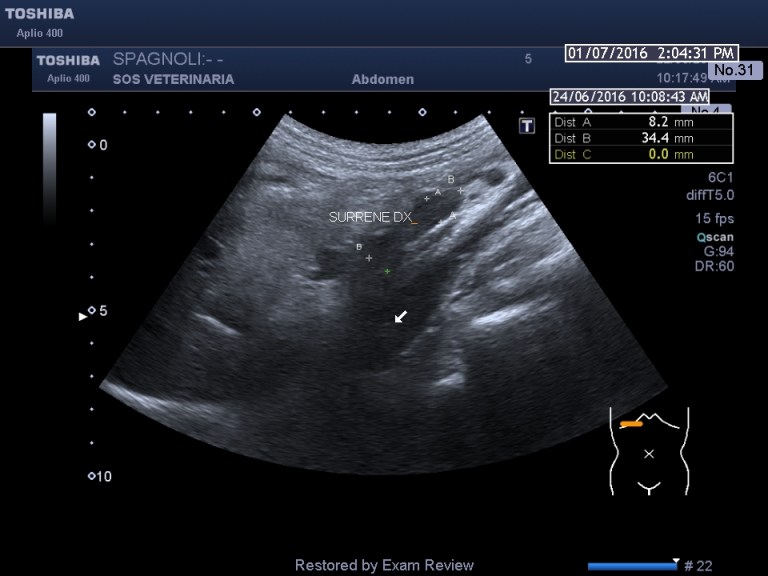

Esame ecografico.

evidente iperplasia ,morfologia conservata

nella destra asse lungo i valori superano di poco il riferimento

anche in asse corto si supera il valore di riferimento